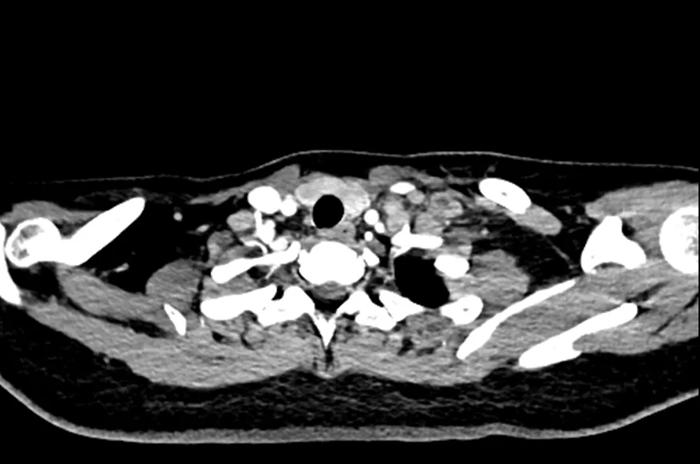

Hình ảnh chụp CT của nữ sinh 20 tuổi

Gần đây, một phụ nữ ngoài 20 tuổi đến khám tại Bệnh viện Nhân dân Đông Hoản (Quảng Đông, Trung Quốc) vì phát hiện khối u ở cổ trái trong khoảng một tuần.

Trước đó, cô cảm thấy vùng cổ đau nhẹ và sờ thấy một khối cứng kích thước gần bằng quả trứng gà. Khối u ấn vào có cảm giác đau nhưng không đỏ, không sưng. Điều đáng nói là cô không hề có triệu chứng tiêu hóa rõ ràng như đau bụng, đầy hơi hay sốt, ăn uống và đại tiện vẫn bình thường.

Sau khi nhập viện để kiểm tra toàn diện, bác sĩ tiến hành nội soi dạ dày và sinh thiết hạch cổ . Kết quả giải phẫu bệnh cho thấy bệnh nhân mắc ung thư biểu mô tuyến kém biệt hóa , trong đó có thành phần ung thư tế bào nhẫn – một dạng ung thư dạ dày ác tính cao.

Chụp CT cho thấy khối u đã di căn toàn thân , không còn chỉ định phẫu thuật. Các bác sĩ chỉ có thể đề nghị điều trị bằng hóa trị, xạ trị hoặc liệu pháp miễn dịch nhằm kiểm soát bệnh.